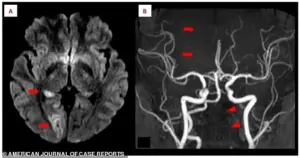

Doctors, upon examining her brain scans, discovered acute ischemic stroke in the right occipital lobe, a region critical for visual processing.

The MRI images, marked with arrows, revealed bright white spots—evidence of brain tissue deprived of oxygen due to blocked blood flow.

The scans also exposed a more ominous detail: a missing section of the right posterior cerebral artery, the key blood vessel supplying the brain.

This artery, normally a smooth, continuous line, had a distinct gap, indicating a blockage.

Further investigation revealed a crescent-shaped blood clot embedded within the left vertebral artery, a vital conduit for blood to reach the brain.

This artery, visible in the scans, appeared faint and thin, signaling restricted blood flow.